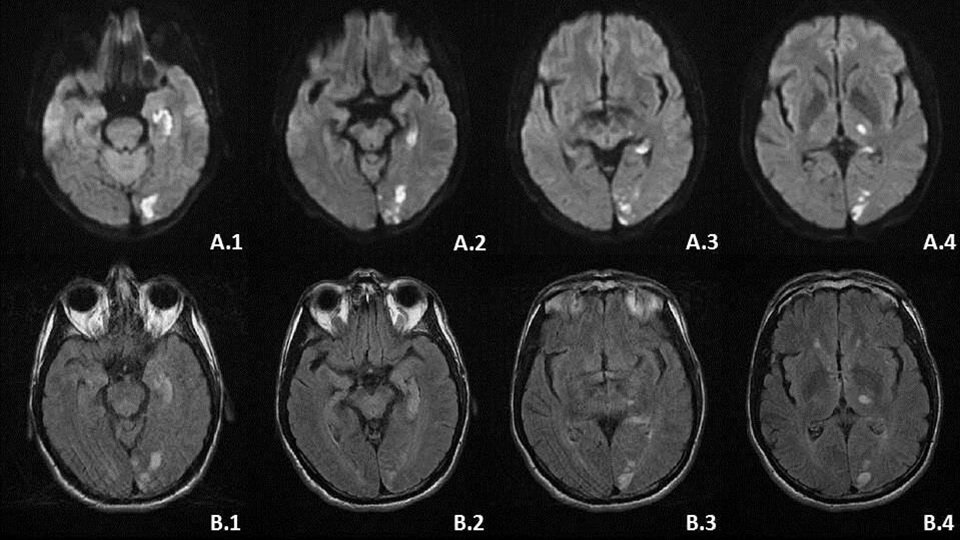

Given these findings, this patient was discussed with the neurosurgical on call team. He was commenced on oral dexamethasone and transferred urgently to the tertiary neurosurgical centre for urgent review. Magnetic Resonance Imaging (MRI) (Figure 2) of his brain and orbits detailed further significant vascular involvement, including invasion of the right cavernous sinus, encasement of the right supraclinoid ICA, proximal right M1 MCA and foetal posterior cerebral artery (PCA). The A1 ACA segment was absent or occluded and the right M1 MCA was severely stenosed. The mass directly abutted the lateral surface of the right optic nerve but without evidence of involvement or chronic nerve atrophy (Figure 3).

Formal ophthalmology assessment noted improvement in his VA to 6/6 bilaterally with grade 1-2 optic disc swelling in the left eye without evidence of vascular changes and normal appearance of the right optic disc. Operative management involved craniotomy with dissection of the tumour, retrograde to the direction of the MCA. Gradual tumour bulk removal allowed for visualisation of the optic nerve, ICA, ACA, MCA, posterior communicating artery (PCOM) and anterior communicating artery. Despite the operation’s success in removing the majority of the tumour bulk, the mass was closely adherent to the MCA (and associated perforators),  avernous sinus and right posterior communicating artery. These sections were unable to be completely excised. Biopsies were taken, demonstrating tissue consistent with World Health Organisation (WHO) grade 1 meningioma without invasion into brain parenchyma.